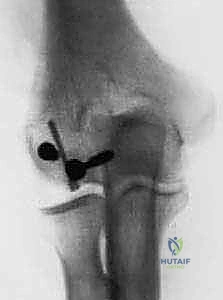

TECH FIG 3 • B. Postoperative radiographs illustrate repair of the lateral epicondyle and fracture fixation.

Closure

- Lateral Epicondyle Repair: If a lateral epicondyle osteotomy was performed, or if it was avulsed, it must be repaired meticulously. A tension band technique or a small plate and screws can be used to achieve stable fixation.

- Olecranon Osteotomy Repair: If an olecranon osteotomy was performed, repair it with a tension band wiring technique or a small olecranon plate and screws.